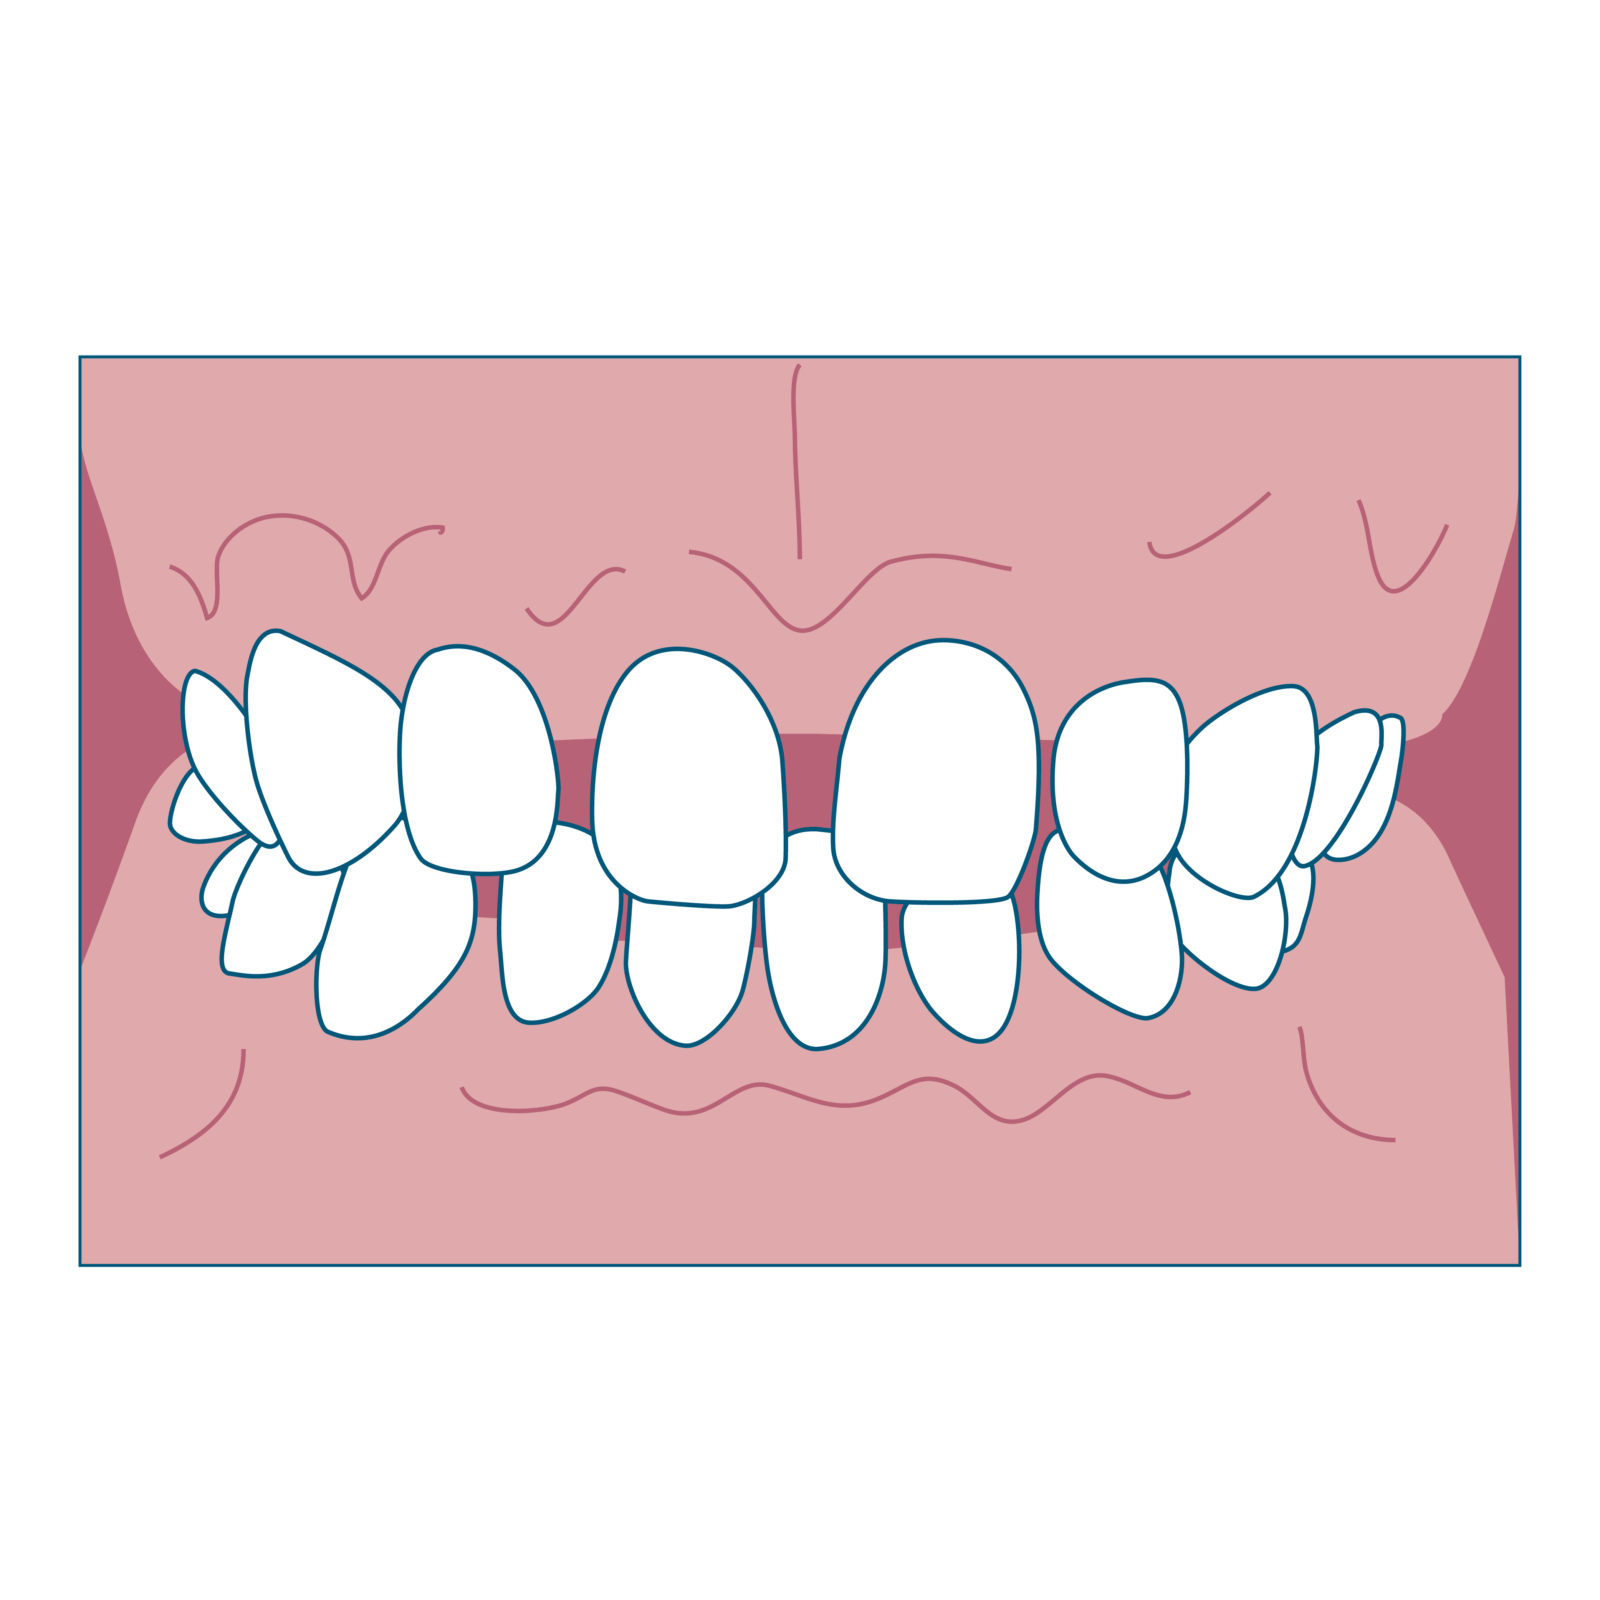

⑤ 開咬(奥歯をかみ合わせても前歯が閉じない)

特徴

- 奥歯がかみ合っても前歯の間にすき間ができる

- 舌の位置や発音に影響が出ることも

始め時

5〜8歳ごろに生活習慣や舌の癖を改善するのがカギです。舌で前歯を押す癖や、口呼吸、指しゃぶりが原因のことが多いです。

ワンポイント

癖が残ったままだと、せっかく矯正しても後戻りしやすいので注意が必要です。